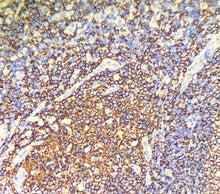

CD20 est une protéine transmembranaire non glycosylée, spécifiquement exprimée à la surface des précurseurs des lymphocytes B et des lymphocytes B matures, mais dont l’expression disparaît lors de la différenciation en plasmocytes.

L’anticorps CD20 identifie fortement les cellules de Reed-Sternberg prédominantes dans la maladie de Hodgkin. Étant donné qu’il ne colore ni les histiocytes ni les plasmocytes et qu’il n’est pas détecté dans les tumeurs à cellules T, il constitue un marqueur hautement spécifique des lymphomes à cellules B.

Contrôle positif : Tissu amygdalien